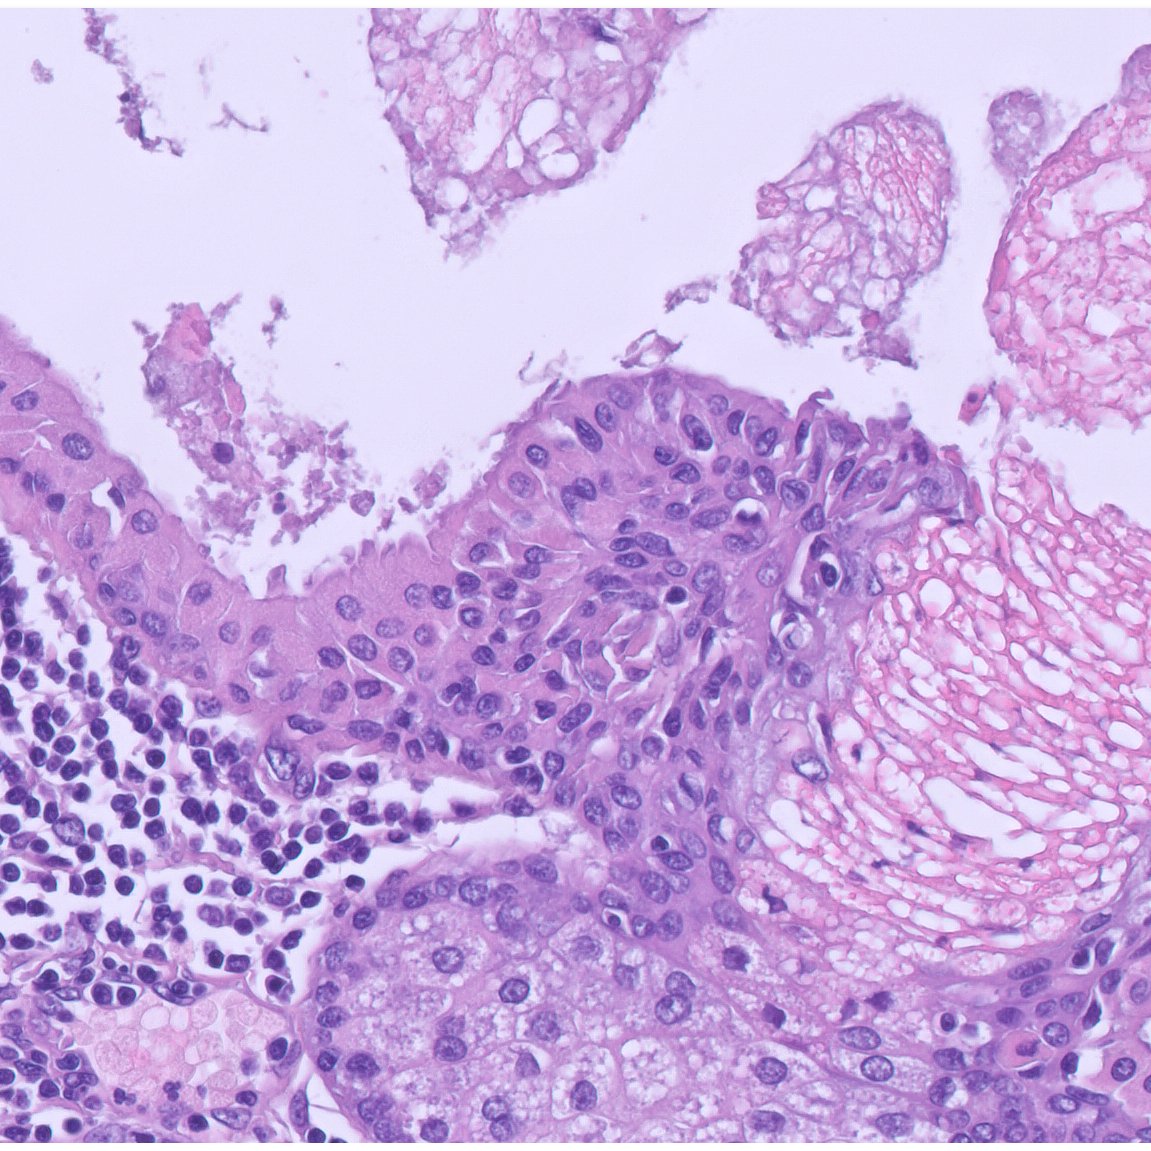

Red-purple skin nodule on elbow.

What systemic issues are associated with this?